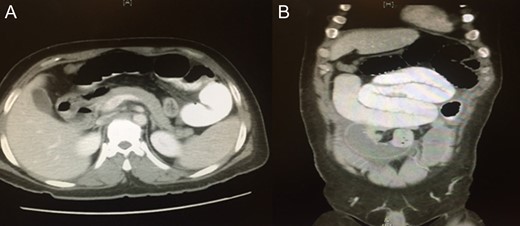

Blood was drawn for a complete blood count, urea and electrolytes, liver function test, coagulation profile, serum glucose level, carcinoembryonic antigen and cancer antigen, and the results were all within normal limits. An initial abdominal X-ray showed multiple air fluid levels and a dilated bowel (Fig. 1A and B). A computed tomography scan of the abdomen and pelvis showed small bowel obstruction to the level of the proximal ileal loops, with a transition point between the dilated proximal loops and the collapsed terminal ileal loops (Fig. 2A and B).

A computed tomography of the abdomen and pelvis showing small bowel obstruction at the level of the proximal ileal loops, with a transition point between dilated proximal loops and the collapsed terminal ileal loops.